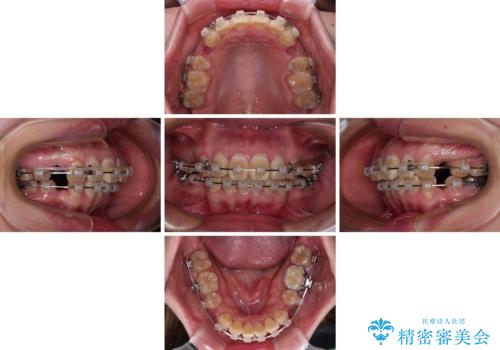

- 20代女性

- クリアブラケット

- 2年4ヶ月

- 口元の閉じにくさと、前歯のでこぼこの歯並びを気にして来院された患者様です。

口元を積極的に引っ込めるために、上下左右の小臼歯計4本を抜歯することとしました。

4本の歯を抜歯したことで、飛び出していた口元が引っ込み、横顔が大きく改善されました。